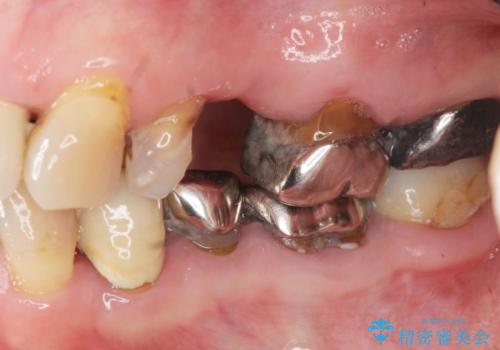

- 見た目の悪い銀歯や虫歯、歯の欠損、全体的な治療を希望されて来院されました。

インプラント治療や根管治療・セラミック治療を総合的に考えた精度の高い治療を計画し、しっかり噛めるようになるのはもちろん長期的な予後や審美性の向上を考えた全顎的な治療を実践していきます。